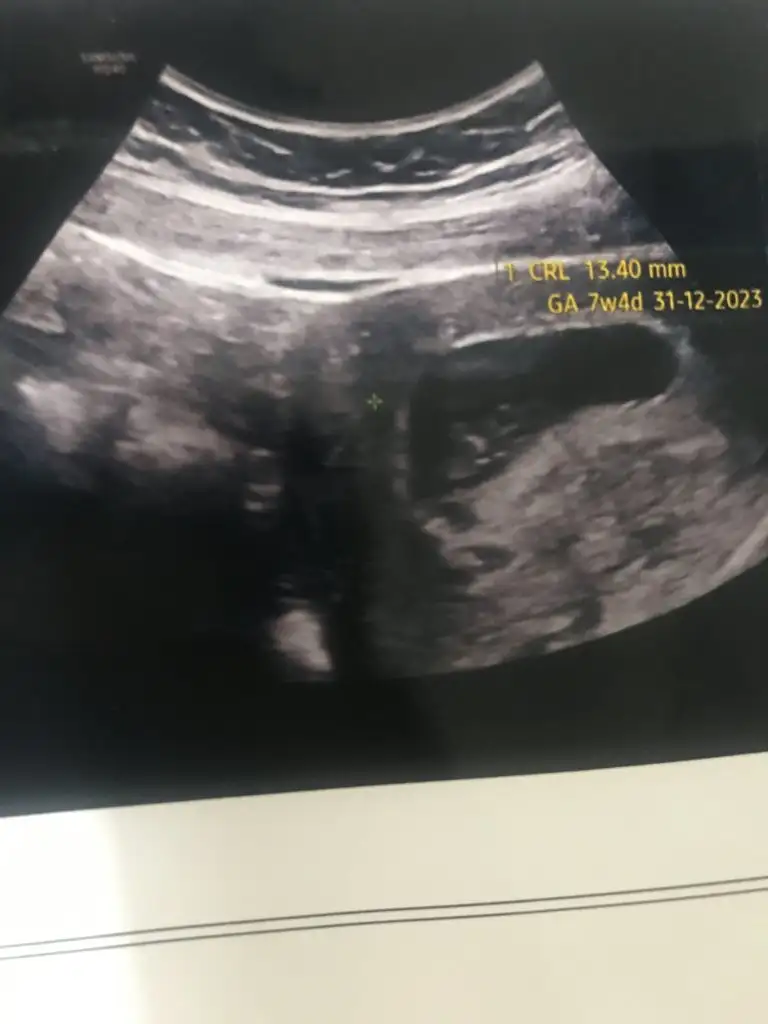

Bebek şükür iyi.

9+4 olmuş.